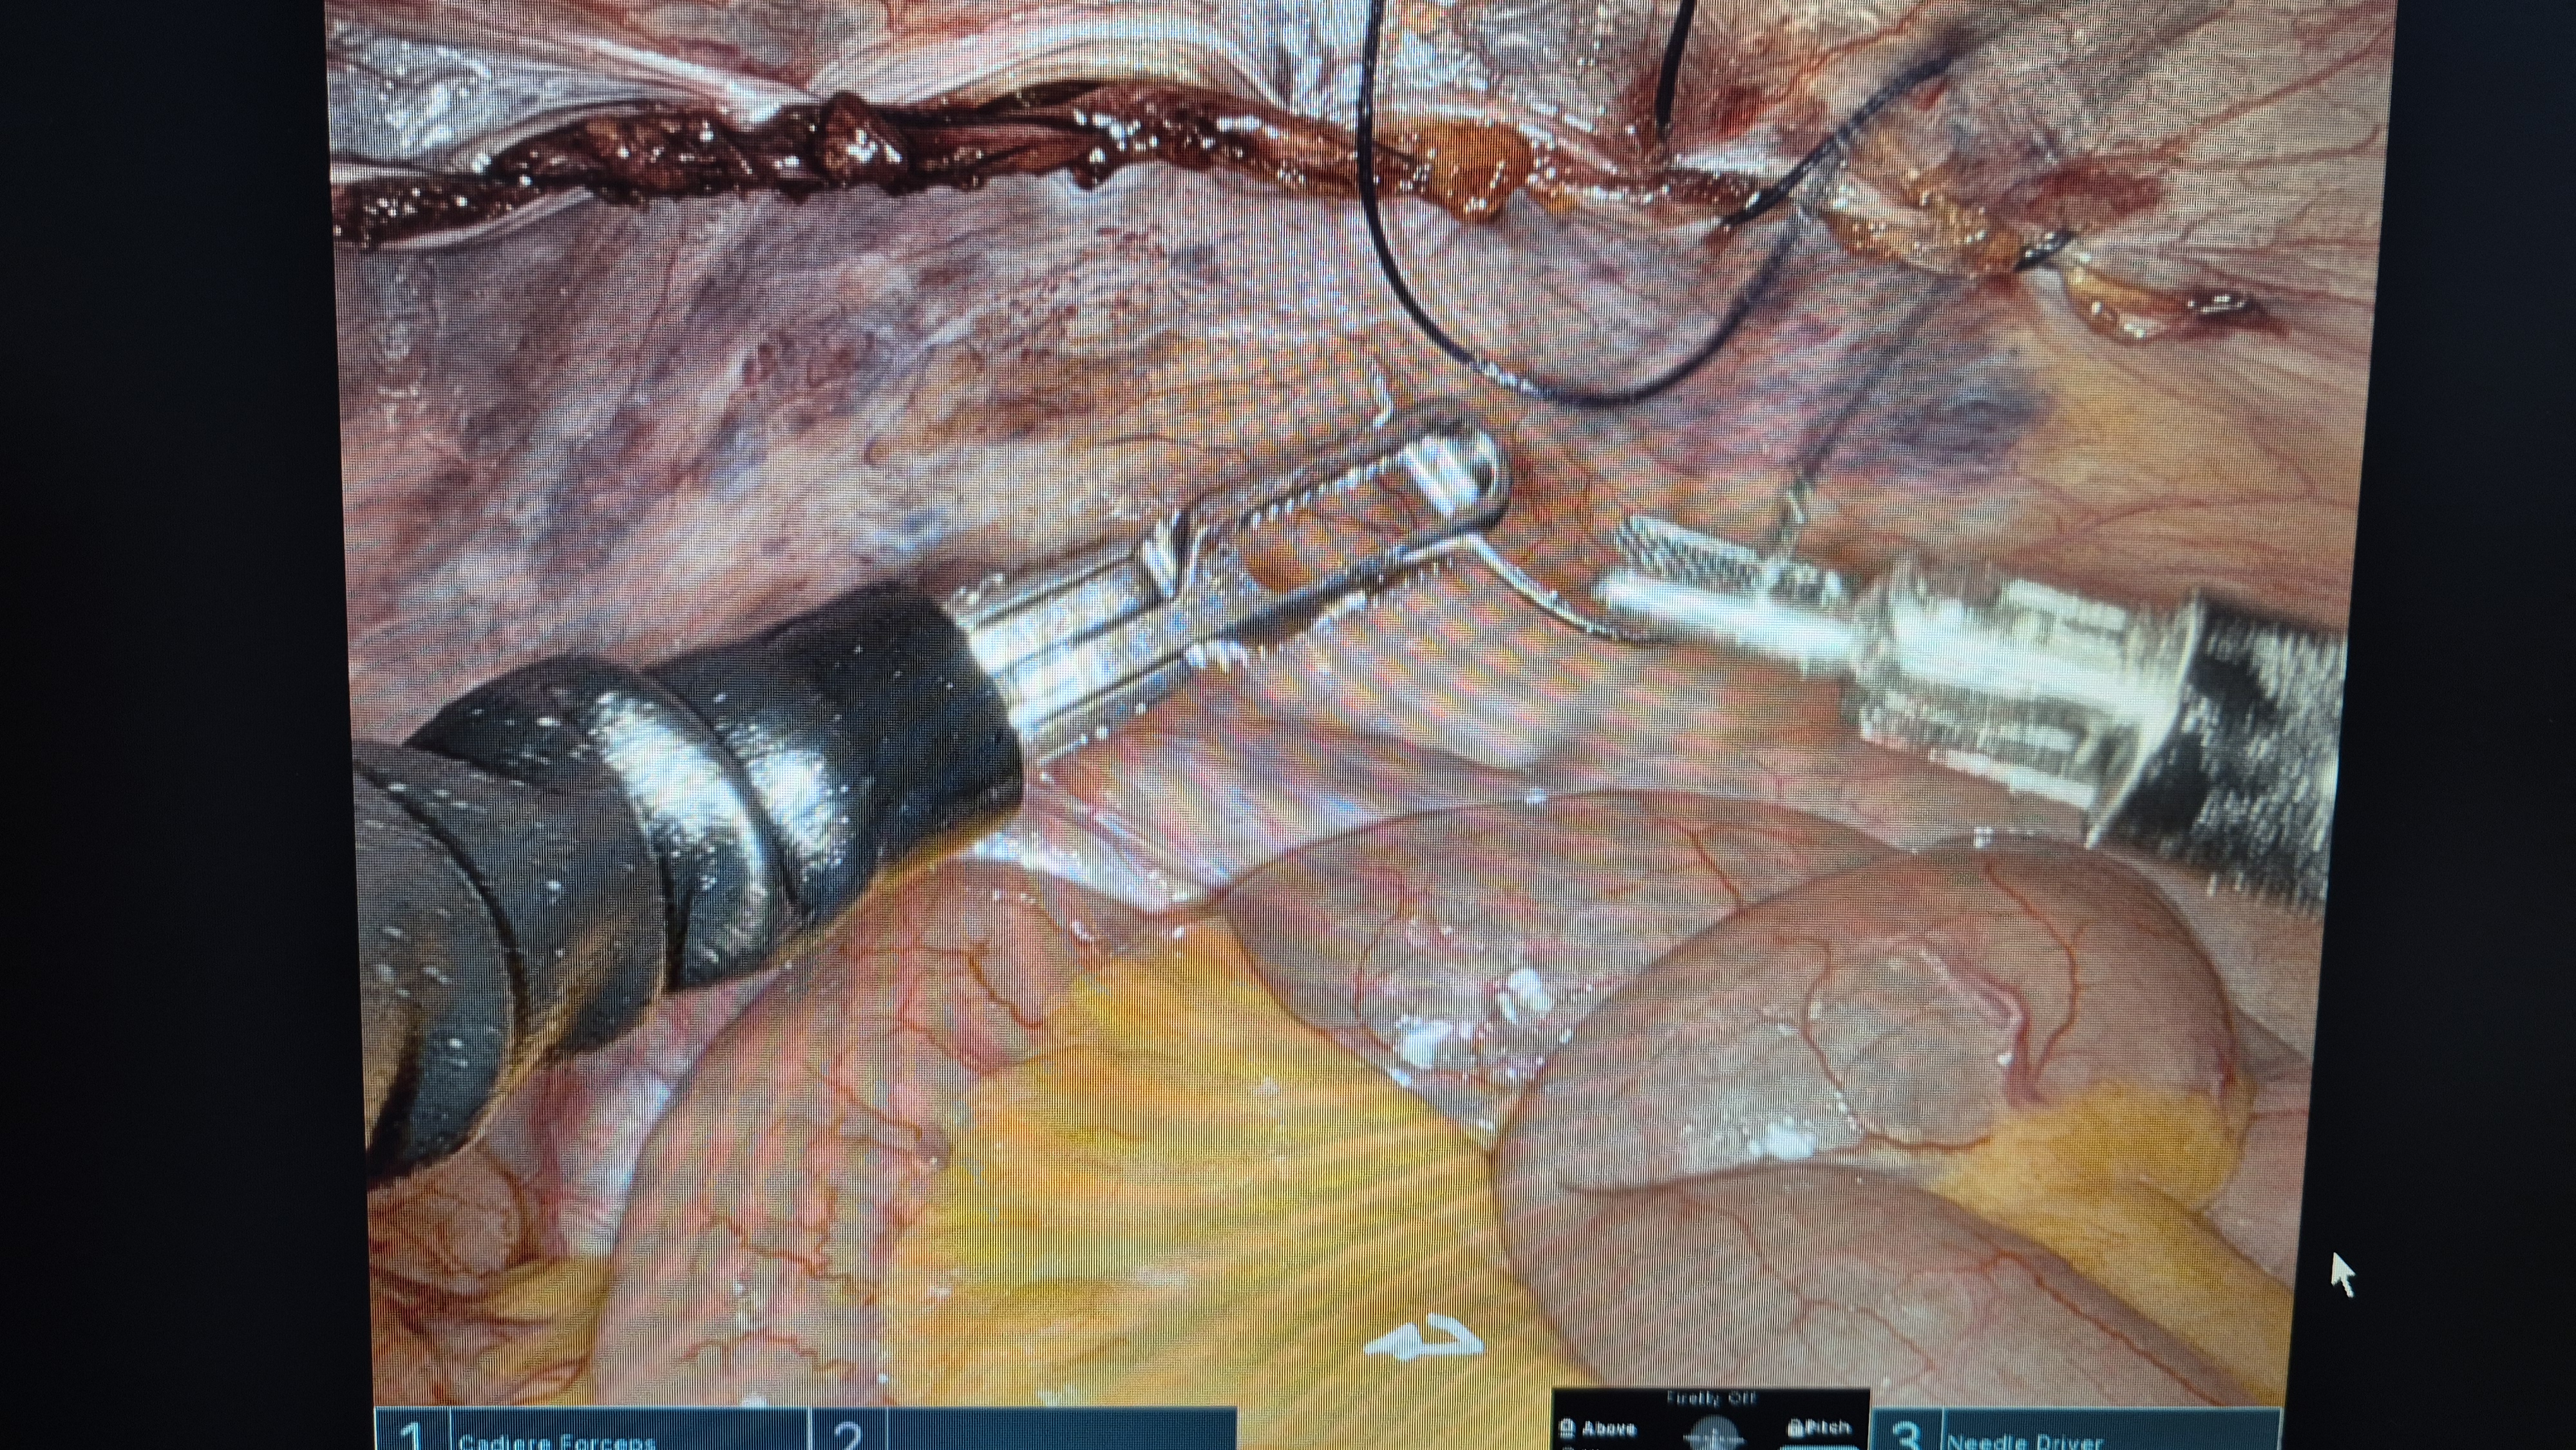

메쉬로 고정.

복막 닫기.